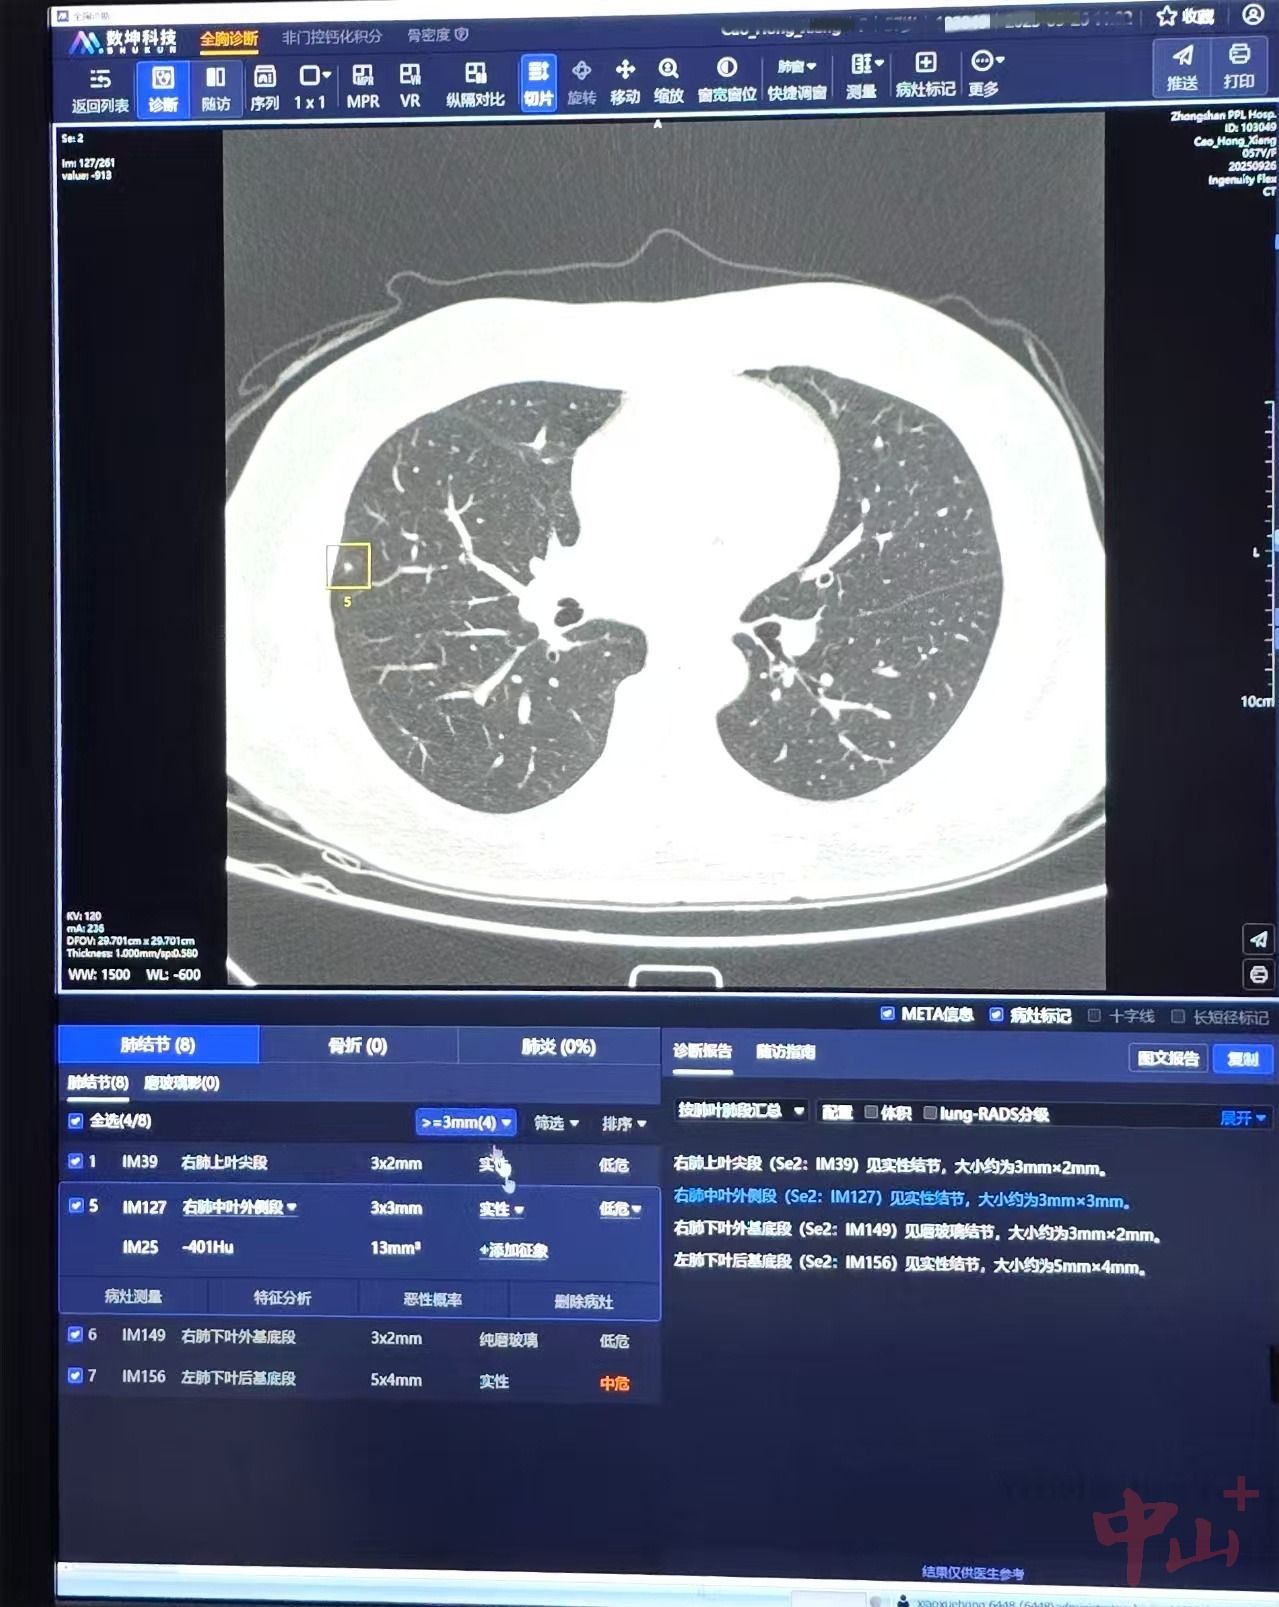

以往,医生在进行肺部CT检查时,人工阅片易遗漏≤5mm的小结节,漏诊率达30%。市人民医院引进的“肺结节AI”则可自动检测、定位、定量分析和良恶性风险评估肺部结节,它就像一位经验极其丰富的“读片专家”,能快速、准确地分析患者的医学影像,帮助破解“大海捞针”难题,锁定早期恶性结节。

“AI系统的判断标准一致,不会疲劳,能发现微小病灶,减少人为主观差异,同时,AI可以快速处理大量图像,缩短重建和出报告时间,患者等候时间也相应减少。”市人民医院医学影像中心主任、主任医师肖学红表示。